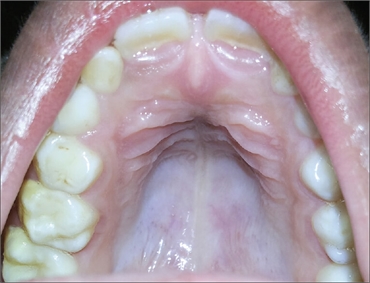

What is High-arched palate or Gothic palate?

High-arched palate, also known as high-vaulted palate, gothic palate or bubble palate is a condition when the roof of the mouth, or palate is high and narrow. It currently affects approximately 30% of people residing in the U.S. In some it is congenital, while in others it is a condition formed after birth due to certain behaviors. In addition, it is sometimes a symptom of of the following syndromes:

In order to diagnose pseudo-cleft palate, doctors look at several measurements in the mouth such as the length, width, height and arch angle of the roof of the mouth. A vaulted palate is one that falls two standard deviations above the average measurements.